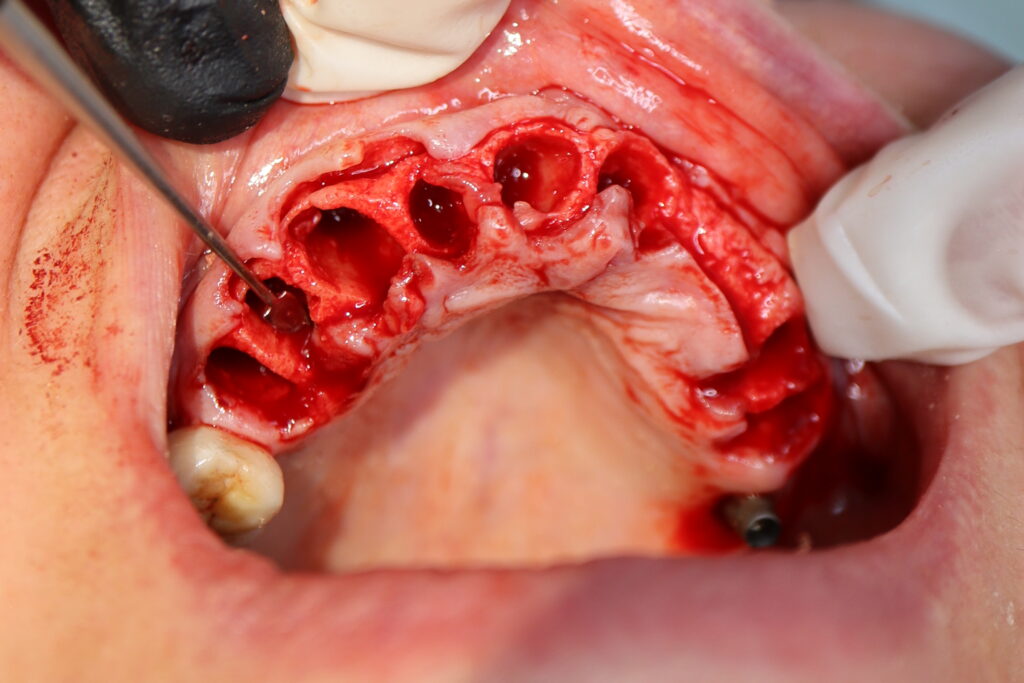

На верхней челюсти были сняты старые мостовидные протезы и удалены зубы, которые находились в неудовлетворительном состоянии.

Установлены 5 имплантантов Straumann BLT и сняты оттиски. Спустя 6 дней на верхней челюсти зафиксирован протез из пластмассы, армированный металлической балкой с опорой на 5 дентальных имплантатов. Ранее у пациента уже были установлены 3 имплантата Straumann.

процесс имплантации

Это фото может содержать тяжелый для восприятия контент